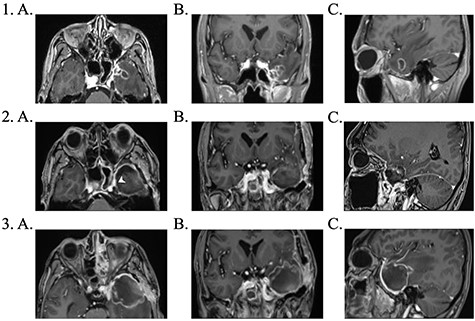

1. Pre-operative contrast enhanced brain MRI: (a) T1 axial view with enhancing lesion; (b) T1 coronal and (c) T1 sagittal. 2. First post-operative contrast enhanced brain MRI showing resection of lesion: (a) T1 axial. Arrow: dural enhancement of sphenoid sinus; (b) T1 coronal and (c) T1 sagittal. 3. Second post-operative contrast enhanced brain MRI following endoscopic re-resection: (a) T1 axial; (b) T1 coronal and (c) T1 sagittal.

The patient underwent further endoscopic re-resection a week following his initial operation. The sphenoid sinus appeared necrotic and a frank collection of fungal matter was observed in the space. Fungal culture from this repeat surgery grew Aspergillus fumigatus and histology was consistent with this diagnosis, demonstrating narrow, septated hyphae with branching angles around 45°. The lateral wall of the sphenoid sinus revealed signs of osteomyelitis from chronic Aspergillus infection. There was no evidence of mucormycosis from any culture. Following sensitivity reports, the antifungal agent was changed to voriconazole due to acute kidney injury from liposomal amphotericin B.

Further surgical debridement was undertaken due to concerns on MRI of intracerebral abscess formation. The appearance at theatre was that of a hematoma, and bacterial cultures yielded no growth.